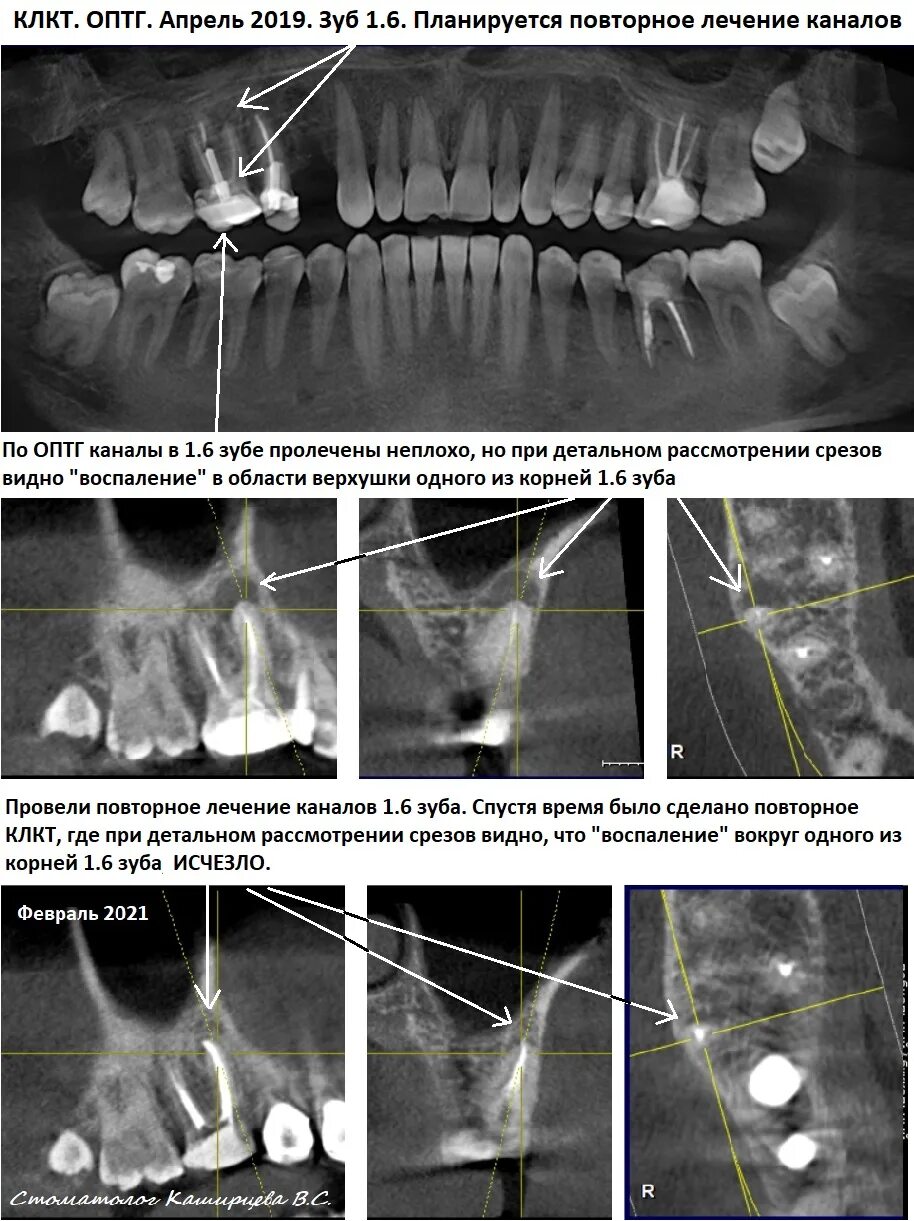

Кл кт